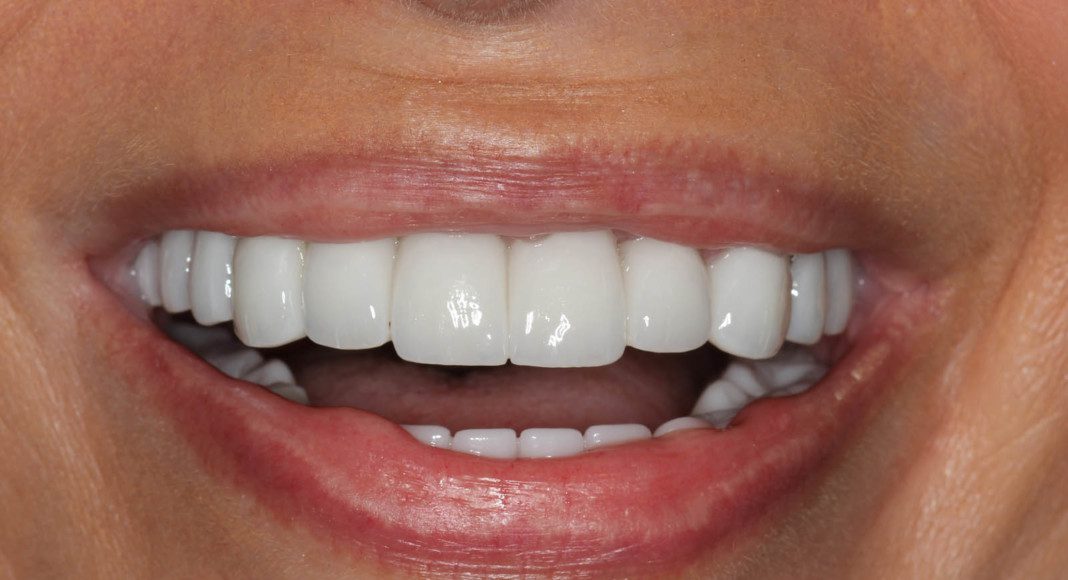

She had sequential or transitional treatment meaning because we had some many hurdles to overcome (large teeth with small bone, bone resorption, impacted teeth, malocclusion – jumbled dentition, poor aesthetics, reluctant patient) we had to perform treatment in sections. She continued to wear removable teeth for several months. This is a picture of when she finally had all fixed temporaries. It is at this point when patients become very happy. Remember, it took decades for the problems to manifest. Rushing to give her fixed teeth too fast is very likely to ruin the final outcome.

Frontal view of wax prototype in the patient’s mouth. In her case, we agreed that the teeth were too long. The laboratory then modifies the wax-up to shorten the teeth. 50% of the time we try the modified temporary in. When changes are small, we can advise the lab and they make those changes before converting to zirconia. When changes are many, or the patient wants to see them again, a second wax prototype is tried in for approval.

Frontal view – upper zirconia bridges with lower acrylic temporary. We are now ready to finish the lower jaw.